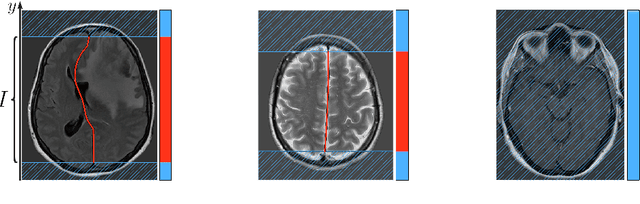

Abstract:Midline shift (MLS) is a well-established factor used for outcome prediction in traumatic brain injury, stroke and brain tumors. The importance of automatic estimation of MLS was recently highlighted by ACR Data Science Institute. In this paper we introduce a novel deep learning based approach for the problem of MLS detection, which exploits task-specific structural knowledge. We evaluate our method on a large dataset containing heterogeneous images with significant MLS and show that its mean error approaches the inter-expert variability. Finally, we show the robustness of our approach by validating it on an external dataset, acquired during routine clinical practice.